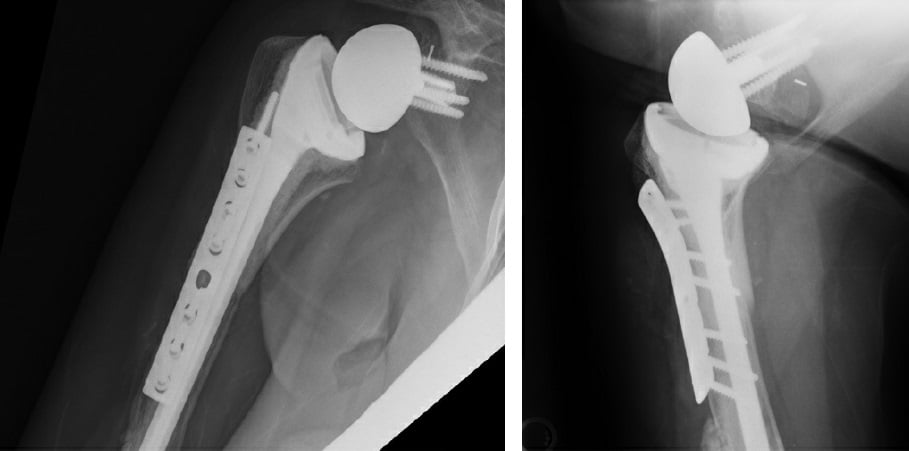

Next, the final implant was trialed and a distal screw was removed in order to seat the implant. Satisfied with our length and motion (FF 140°, ER 70°), we cemented the humerus and seated the final components. Final fluoroscopy demonstrated an appropriate intramedullary cement mantle, with some cement extrusion distally out of a breach in the humeral diaphysis incurred during cement removal (Fig. 4). The cement was left in situ to avoid additional morbidity of removal. The posterior rotator cuff tendons (teres minor and infraspinatus) were repaired to the allograft rotator cuff tendon stumps to empower ER.

Figure 4: Postoperative X-rays show APC proximal humerus reconstruction.

The patient adhered to our postoperative protocol: weeks 0–6, use sling with distal range of motion (ROM) and Codman pendulum exercises only; weeks 6–12, discontinue sling, with a goal of FF 140° and ER 45°; weeks 12+, continue pursuit of ROM, strength, and endurance. Her postoperative course was uncomplicated aside from feelings of fullness around the area of extramedullary cement extravasation. Radial nerve function was normal. At 1-year follow-up, she reported satisfaction with her outcome, reporting occasional soreness with activity but no resting or nighttime pain. She achieved active forward elevation to 120°, ER to 20°, and internal rotation to the greater trochanter.